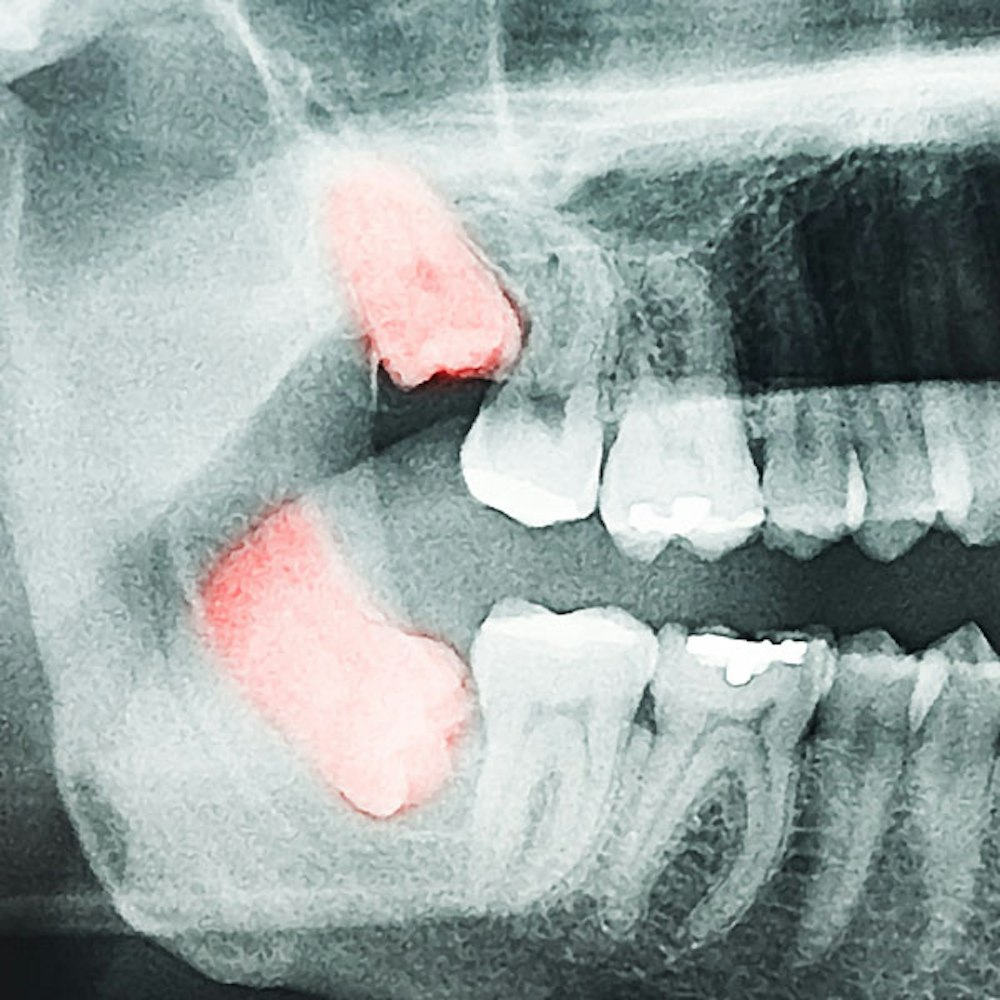

- Advanced imaging for safer, more precise treatment

Take a Closer Look at Tooth Extraction